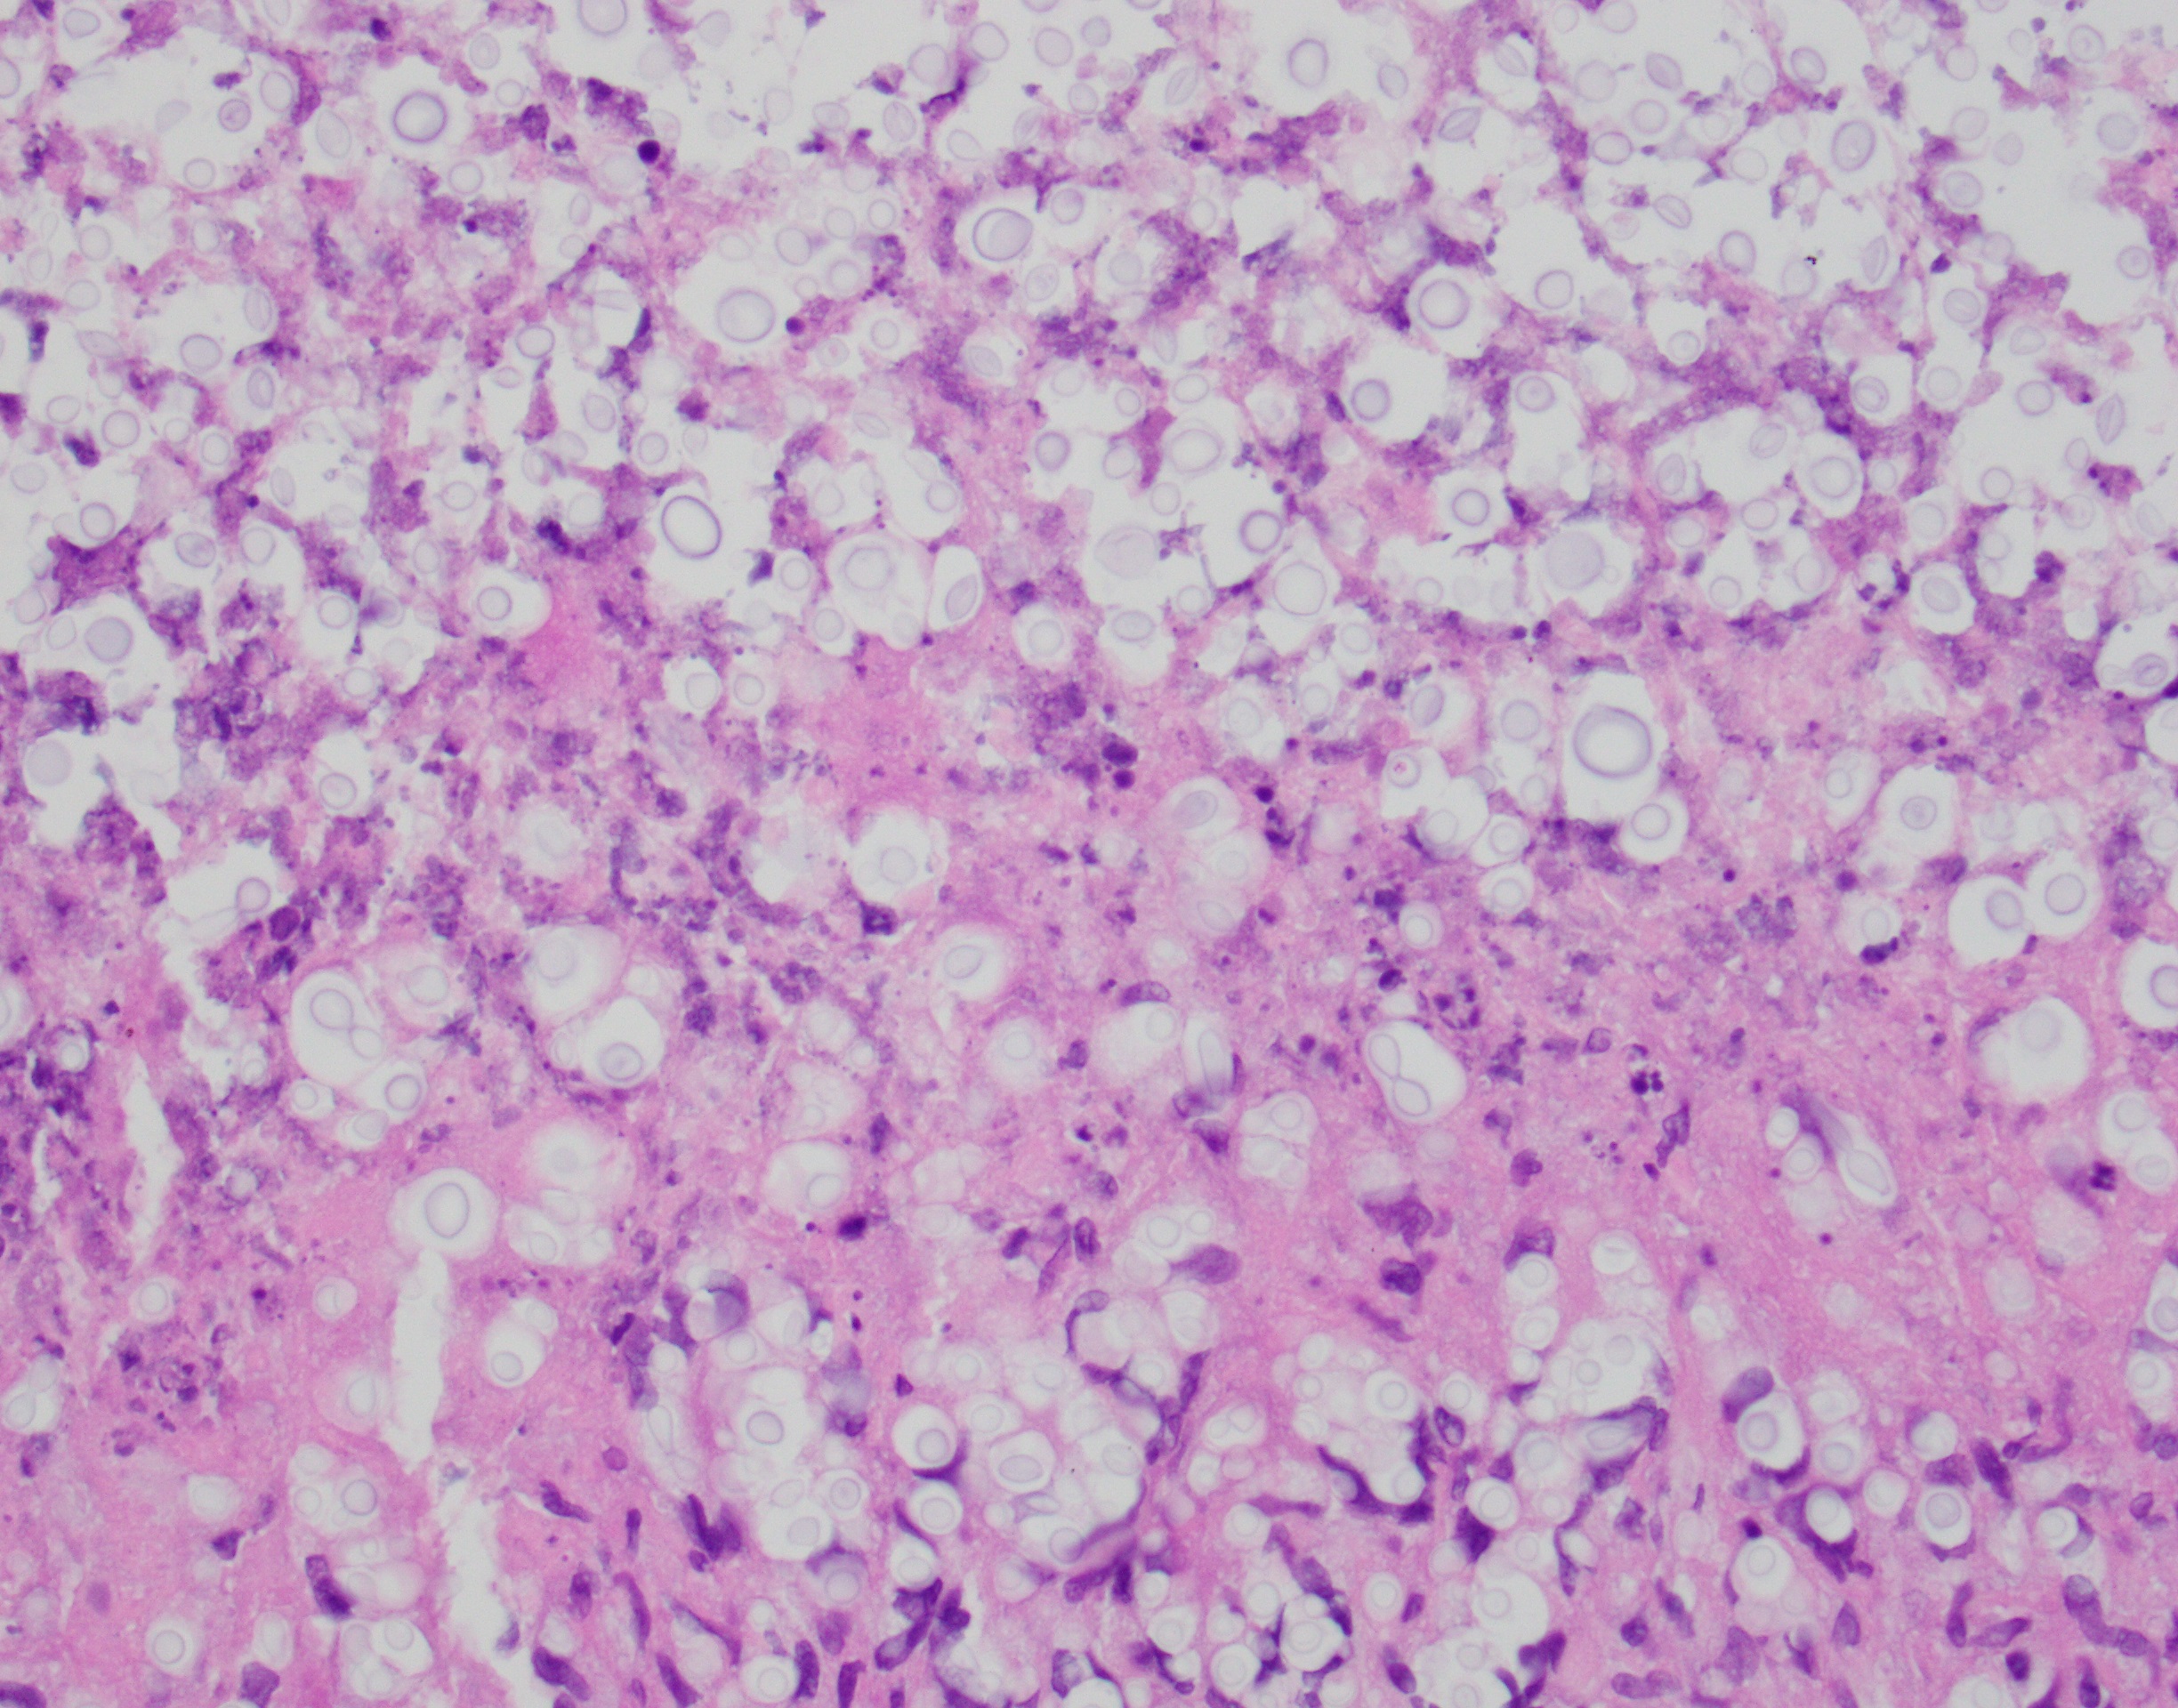

A 68 year old woman presents with a 5.8 cm adrenal mass identified incidentally...